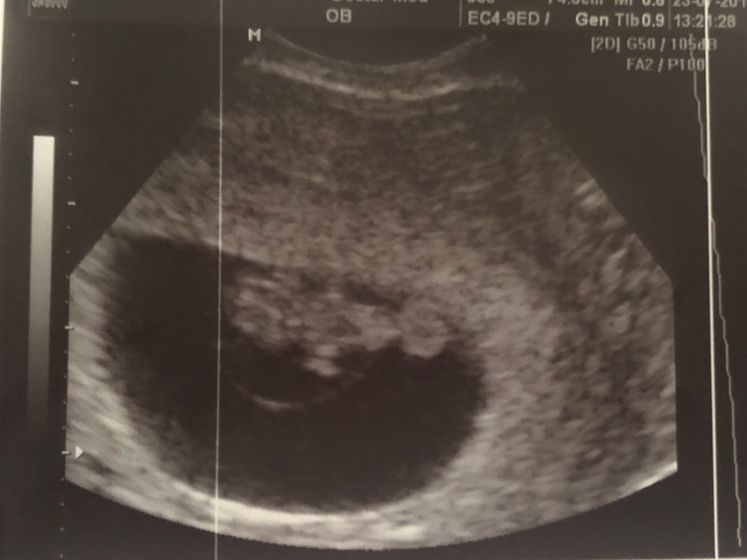

Первое узи и первый поход к гинекологу)

Ну что вот и пришло время сходить на узи, так как по календарю уже 7 неделя, поставили нам конец 8 недели уже, узи чёткое, сердцебиение хорошее 154 уд/мин, СВР 3,0 КТР 1,40

Гинеколог шикарная все объяснила рассказала посмотрела, испугалась когда включили сердечко ) а мама мужа даже заплакала ) длина тела 7,3 см толщина 5,2 см

Ширина тела 7,3 длина шейки 3,4 желточный мешочек 0,44 см